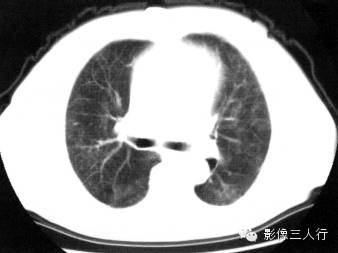

报告书写:胸廓对称,双肺小叶间隔增厚,边缘光滑,肺门及支气管血管束增粗、模糊,纵隔居中,其内未见肿大的淋巴结。心脏大小正常,胸壁软组织未见异常(图1)。

图1间质性肺水肿